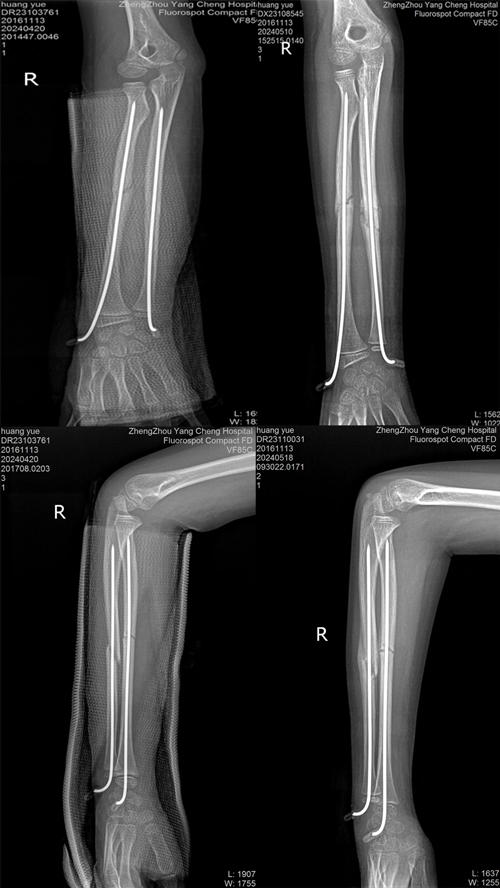

(手術(shù)前)

不開刀也能手術(shù)治療骨折,家有“熊孩子”的一定要看!

(手術(shù)后)

術(shù)中C-型臂機(jī)器透視可見

骨折斷端復(fù)位良好

緊接著用兩枚鋼針

從腕部穿入固定骨折斷端

骨折斷端固定良好